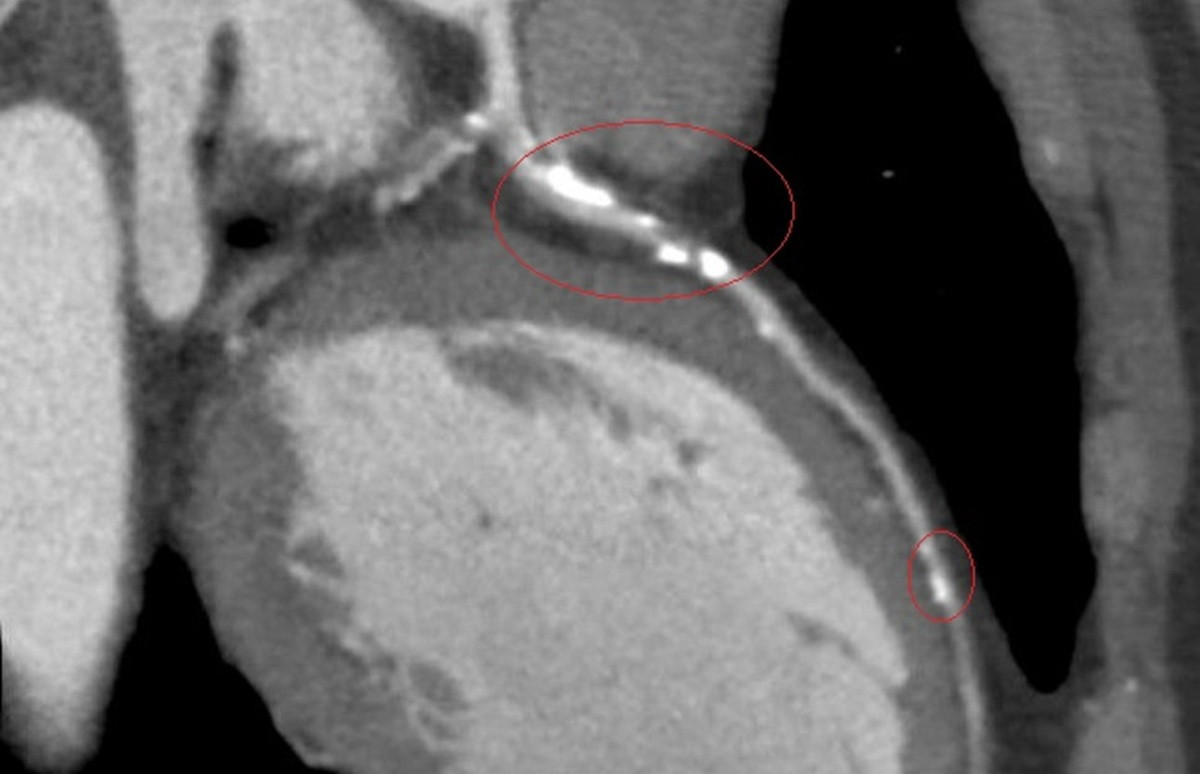

李學林說,醫療團隊透過心導管手術搭配IVL技術,利用震波氣球貼近血管壁發出超聲壓力波,擊碎血管壁的堅硬鈣化斑塊,讓原本僵硬的血管恢復擴張性,為支架放置創造理想的環境,再植入3支支架,使支架能完整展開、貼合血管,降低支架血栓及再狹窄的風險。

李學林指出,臨床上約有三成冠狀動脈疾病患者伴隨中重度血管鈣化狹窄,鈣化讓血管變硬、難以擴張,造成治療挑戰。相較於傳統治療如切割球囊或鑽石旋磨術,IVL對血管壁更為溫和,能有效降低血管破裂與剝離風險,安全性更高,但目前該技術尚未納入健保給付。